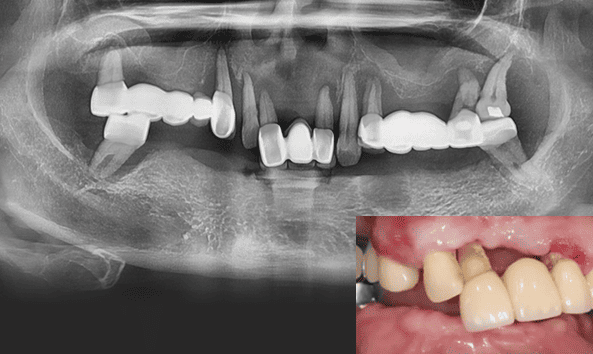

결과로 보여드리는 의료진의 노하우

- 24.12

* 임플란트 시술 시 교합이상, 신경손상, 염증 등의 부작용이 발생할 수 있습니다.

* 개인의 구강 및 치아상태에 따라 치료방법과 수가가 변동될 수 있습니다.

* 해당 사례는 의료법 제56조 2항을 준수하여 작성되었습니다.

* 본원에서 진료받은 환자이며 전후 사진의 인물이 동일인임을 밝힙니다.